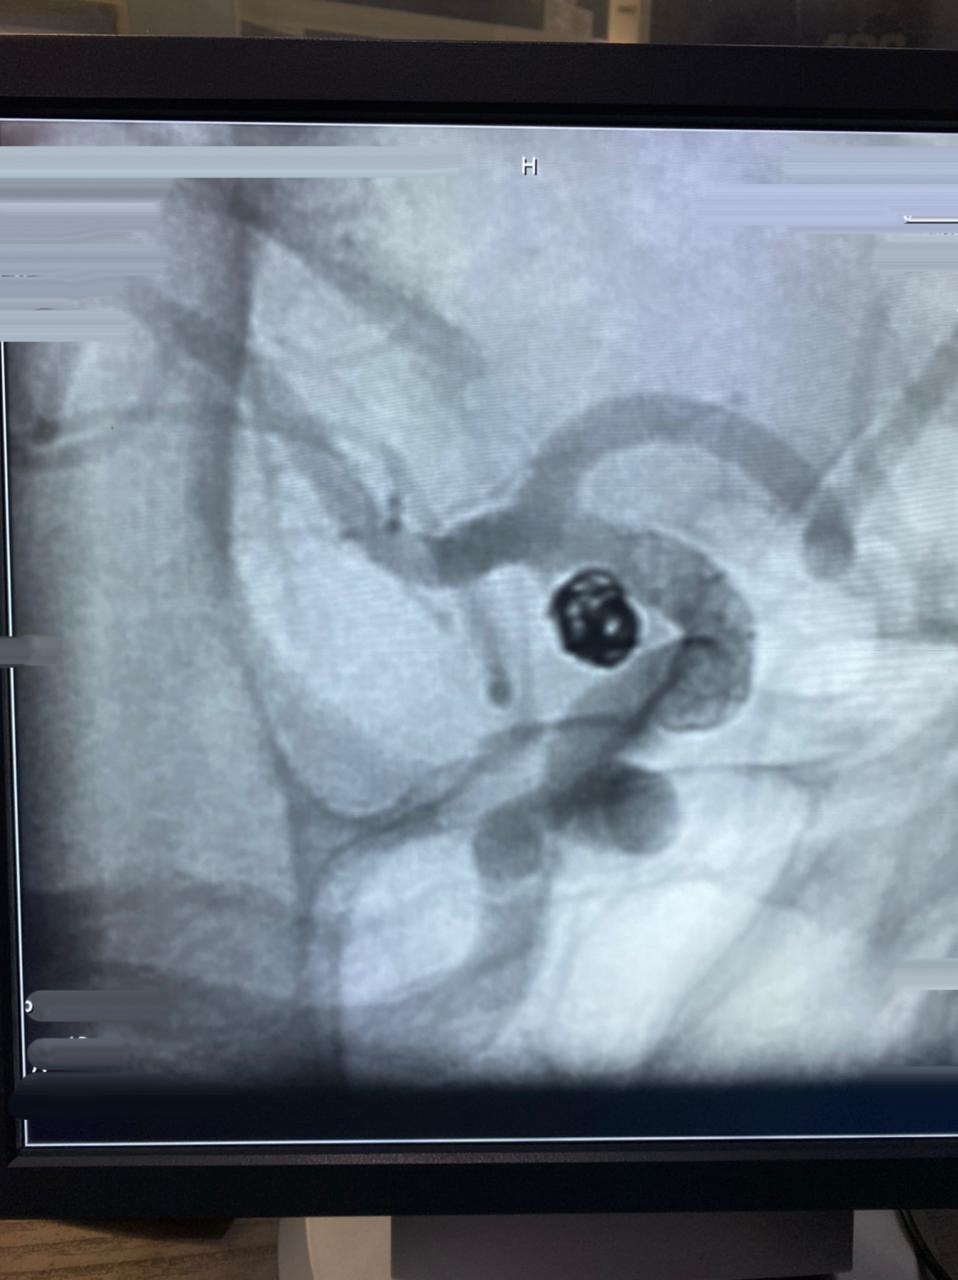

HCorBJ realiza procedimento de Embolização de Aneurisma Cerebral

O procedimento de Embolização de Aneurisma Cerebral é realizado no Setor de Hemodinâmica, sob anestesia geral, com um aparelho de imagem de última geração. O tratamento endovascular, é uma opção minimamente invasiva para as doenças cerebrovasculares.

Dr. Jivago Szpoganicz Sabatini, médico neurologista e neurorradiologista intervencionista que realizou o procedimento destaca, “esse procedimento usa uma tecnologia inovadora, trazendo excelentes resultados, usando o que há de melhor no mundo, em benefício dos pacientes neurológicos.”